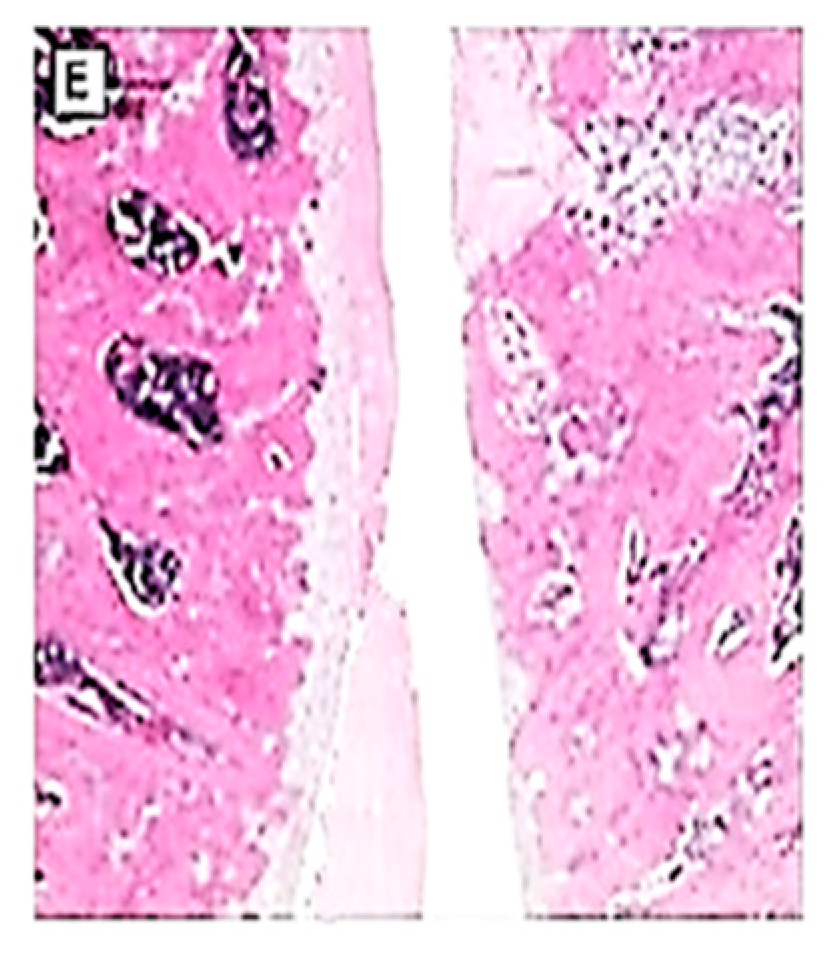

2.5. Histopathological Examination

3.5. Effects on the macroscopic apperance of the articular cartilage